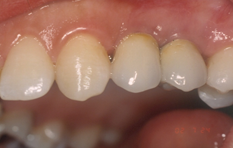

Τελική εικόνα με την τοποθέτηση της προσθετικής κατασκευής πάνω στο οστεο-ενσωματωμένο εμφύτευμα